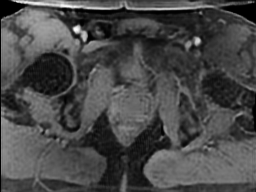

Tables 1 and 2 show our quantitative results: PSNR between the style (image we want to transfer style from) and generated image, SSIM and MS-SSIM between the content (image we want to take structure from) and generated image and finally, our proposed weighted SSIMs. For each style transfer direction and metric, our method consistently outperforms the other approaches. Figures 2 and 3 qualitatively highlight the good results of our method on 2D and 3D datasets. In addition, quantitative results on both figures show that our proposed metric preserves qualitative ordering of results for both style and content. In comparison, metrics such as SSIM struggle to accurately correlate to visual results.

Qualitative evaluation shows that the proposed method leads to sharper images, better content preservation, better localised CE and realistic MRI appearance. Quantitatively, we outperform the other algorithms with each metric, for each style transfer direction. While we expected that adding CE to images would be an easier task than removing CE, we found that for both tasks the method exhibits similarly performing quantitative and qualitative results. The results for style transfer with the kidney data show that when there is clear CE, it is easier to perform style transfer in both directions. However, when style transfer is performed on the prostate data, the model struggles in comparison to the kidney data. This may be due to the enhancement of the prostate being less defined than the kidney data. In figure 3(b), we can see the prostate with CE. Compared to figure 2(b) showing kidneys with CE, it is harder to determine the edges. The two original images shown in figures 3(a) and 3(b) are clear and easy to see some edges of prostate, in other images, it is harder to see the edges of the prostate.

(C) CW-SSIM: 0.71

(S) CW-SSIM: 0.63

(C) CW-SSIM: 0.59

(S) CW-SSIM: 0.41

(C) CW-SSIM: 0.44

(S) CW-SSIM: 0.69

(C) CW-SSIM: 0.94

(S) CW-SSIM: 0.75